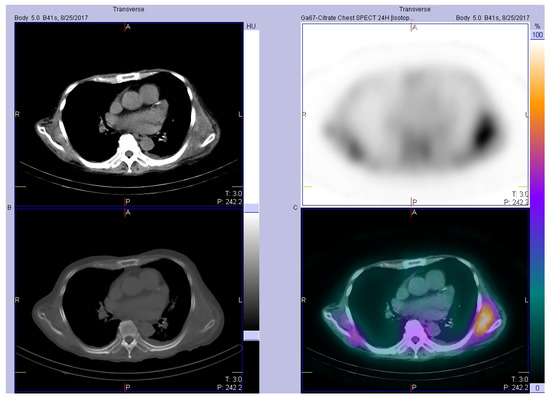

| 8, 2017 (This case) | 70, M | FSGS related ESRD, received 1st renal transplant at age of 40, graft failure at age of 49, and received 2nd renal transplant at age of 68 | Fever of unknown origin | Wide local excision, with no recurrence |